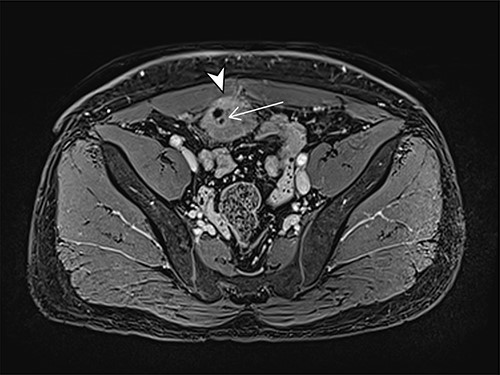

A 41-year-old, previously well, male presented to the emergency department with lower abdominal pain, pyrexia with a temperature of 38.2°C and a palpable suprapubic mass. His relevant background history included an uneventful laparoscopic appendicectomy 2 years prior for acute appendicitis, insulin independent type 2 diabetes and hypertension. He presented with raised inflammatory markers and computed tomography (CT) showing a well circumscribed central pelvis lesion that appeared concerning for a urachal malignancy (Fig. 1). This lesion was closely associated with the dome of the bladder (Fig. 2). This supracystic lesion measured 58 mm × 56 mm with central cystic component of 15 mm in diameter, and contained a 11 mm central calcification. Further characterization with magnetic resonance imaging showed possible extension of this mass to the rectus abdominis without significant lymphadenopathy (Fig. 3). Flexible cystoscopy only found inflammation at the dome. As urachal malignancy could not be unequivocally excluded on imaging studies alone, following multidisciplinary discussion, the decision was made to perform an excision of this lesion.

Axial MRI image of lesion. Arrowhead indicated involvement with the rectus abdominis. Arrow indicates lesion and calcific focus.